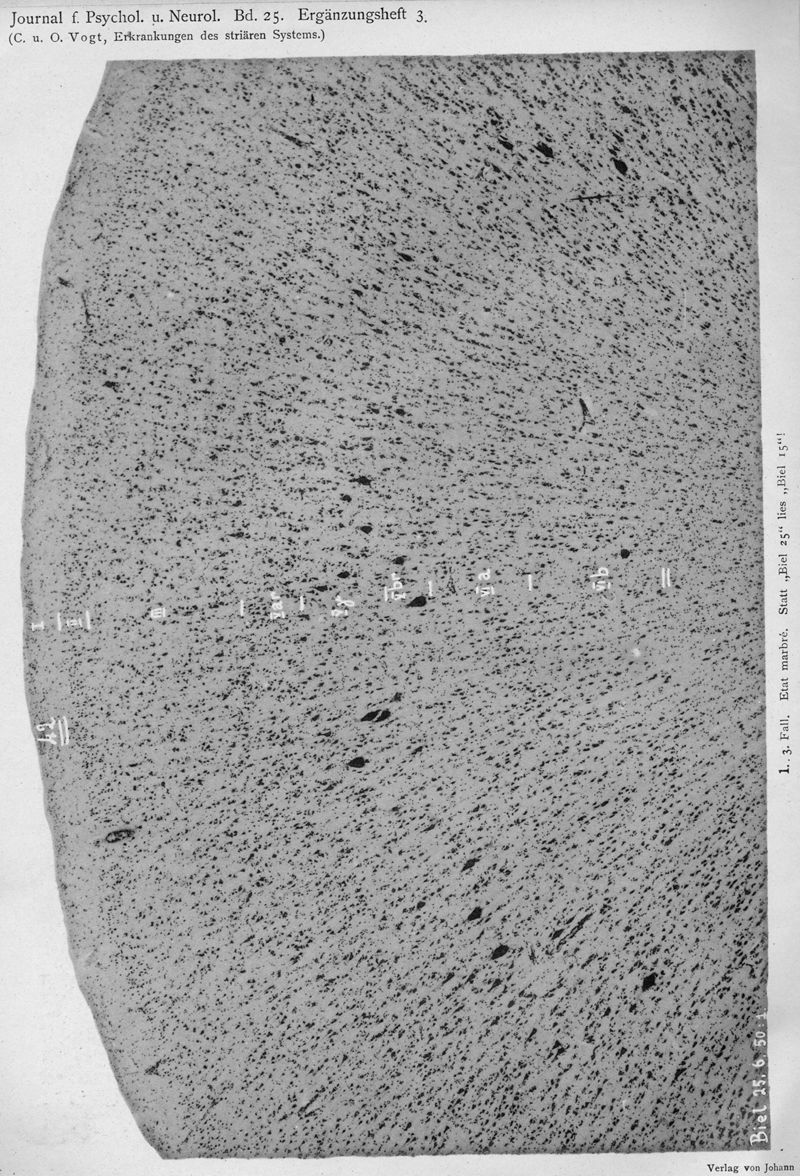

VOGT, Cécile / VOGT, O.

In : Journal für Psychologie und Neurologie,

1920, Vol. 25, pp. 627-846